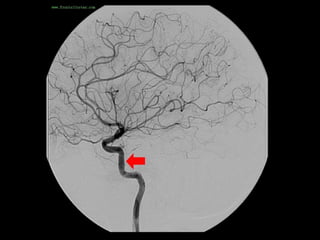

-Anterior temporal branch (best seen in AP view) , a typical

appearance of an anterior temporal branch of the MCA

proximal to the main bifurcation is indicated with the arrow